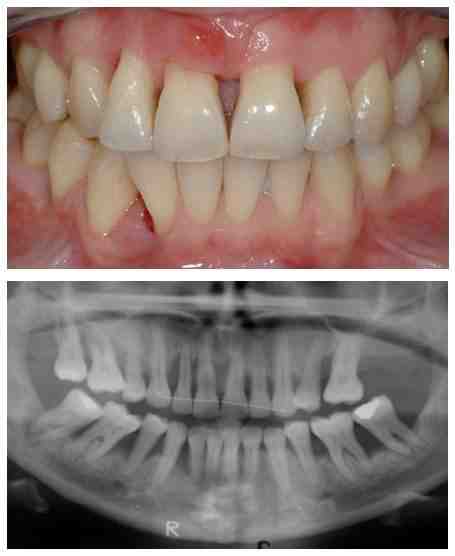

Consequences of not replacing a rear tooth The loss of one tooth, even one tooth, can cause serious and permanent damage to the entire mouth. When you lose a posterior molar, the adjacent teeth are impacted as well, as they lose their surrounding structure and support. See the article : Implant Retained Denture. Unfortunately, this causes your other posterior teeth to dislocate.

Implants can wear out eventually or without proper oral hygiene. Dental implants are not suitable for everyone, few patients may not be eligible for tooth replacement due to their bone health. Dental implants usually require healthy, dense bones. Strong bones in place are a parameter to support dental implants.